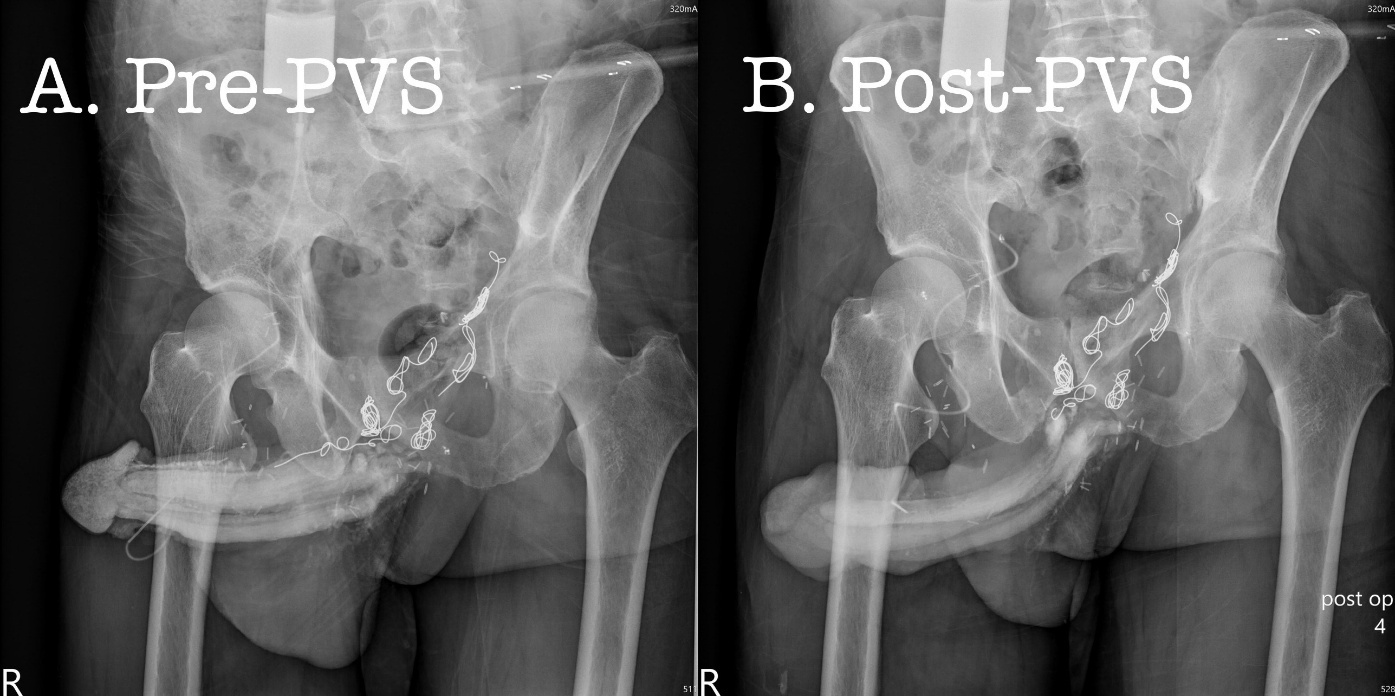

Materials and Methods: From 2013 to 2025, refractory impotence prompted nine men to seek penile venous stripping surgery (PVSS), although 11 episodes were performed elsewhere internationally. They were allocated to groups: SC (n = 5) and CC (n = 4). All received dual cavernosography, in which erection-related veins were anatomically demonstrated, and VODr was confirmed again. On an ambulatory strategy, PVS entailed the venous stripping of one deep dorsal vein and a pair of cavernosal veins after every offensive emissary was firmly fixed closest to the outer tunica using 6-0 nylon. Subsequently, the two pairs of para-arterial veins were segmentally ligated. The abridged 5-item version of the International Index of Erectile Function (IIEF-5) score system and the Erection Hardness Scale (EHS) were used preoperatively, and postoperative follow-up was conducted via the internet annually.

Results: In the SC group (n=5), inserted coils were scattered along the erection-related veins, including the deep dorsal veins (n=4), periprostatic plexus (n=5), iliac vein (n=5), right pulmonary artery (n=2), left pulmonary artery (n=2), and right ventricle (n=1), ended with coil migration out of the right ventricle. PVS has made some improvements in the IIEF-5 score and EHS scale. In the CC group (n=4), there was no benefit of erectile restoration after CC therapy, although no coil travelling radiographically; amazingly, however, erection restoration was unexceptionally attained from 2 weeks to two months after PVS on an ambulatory basis.